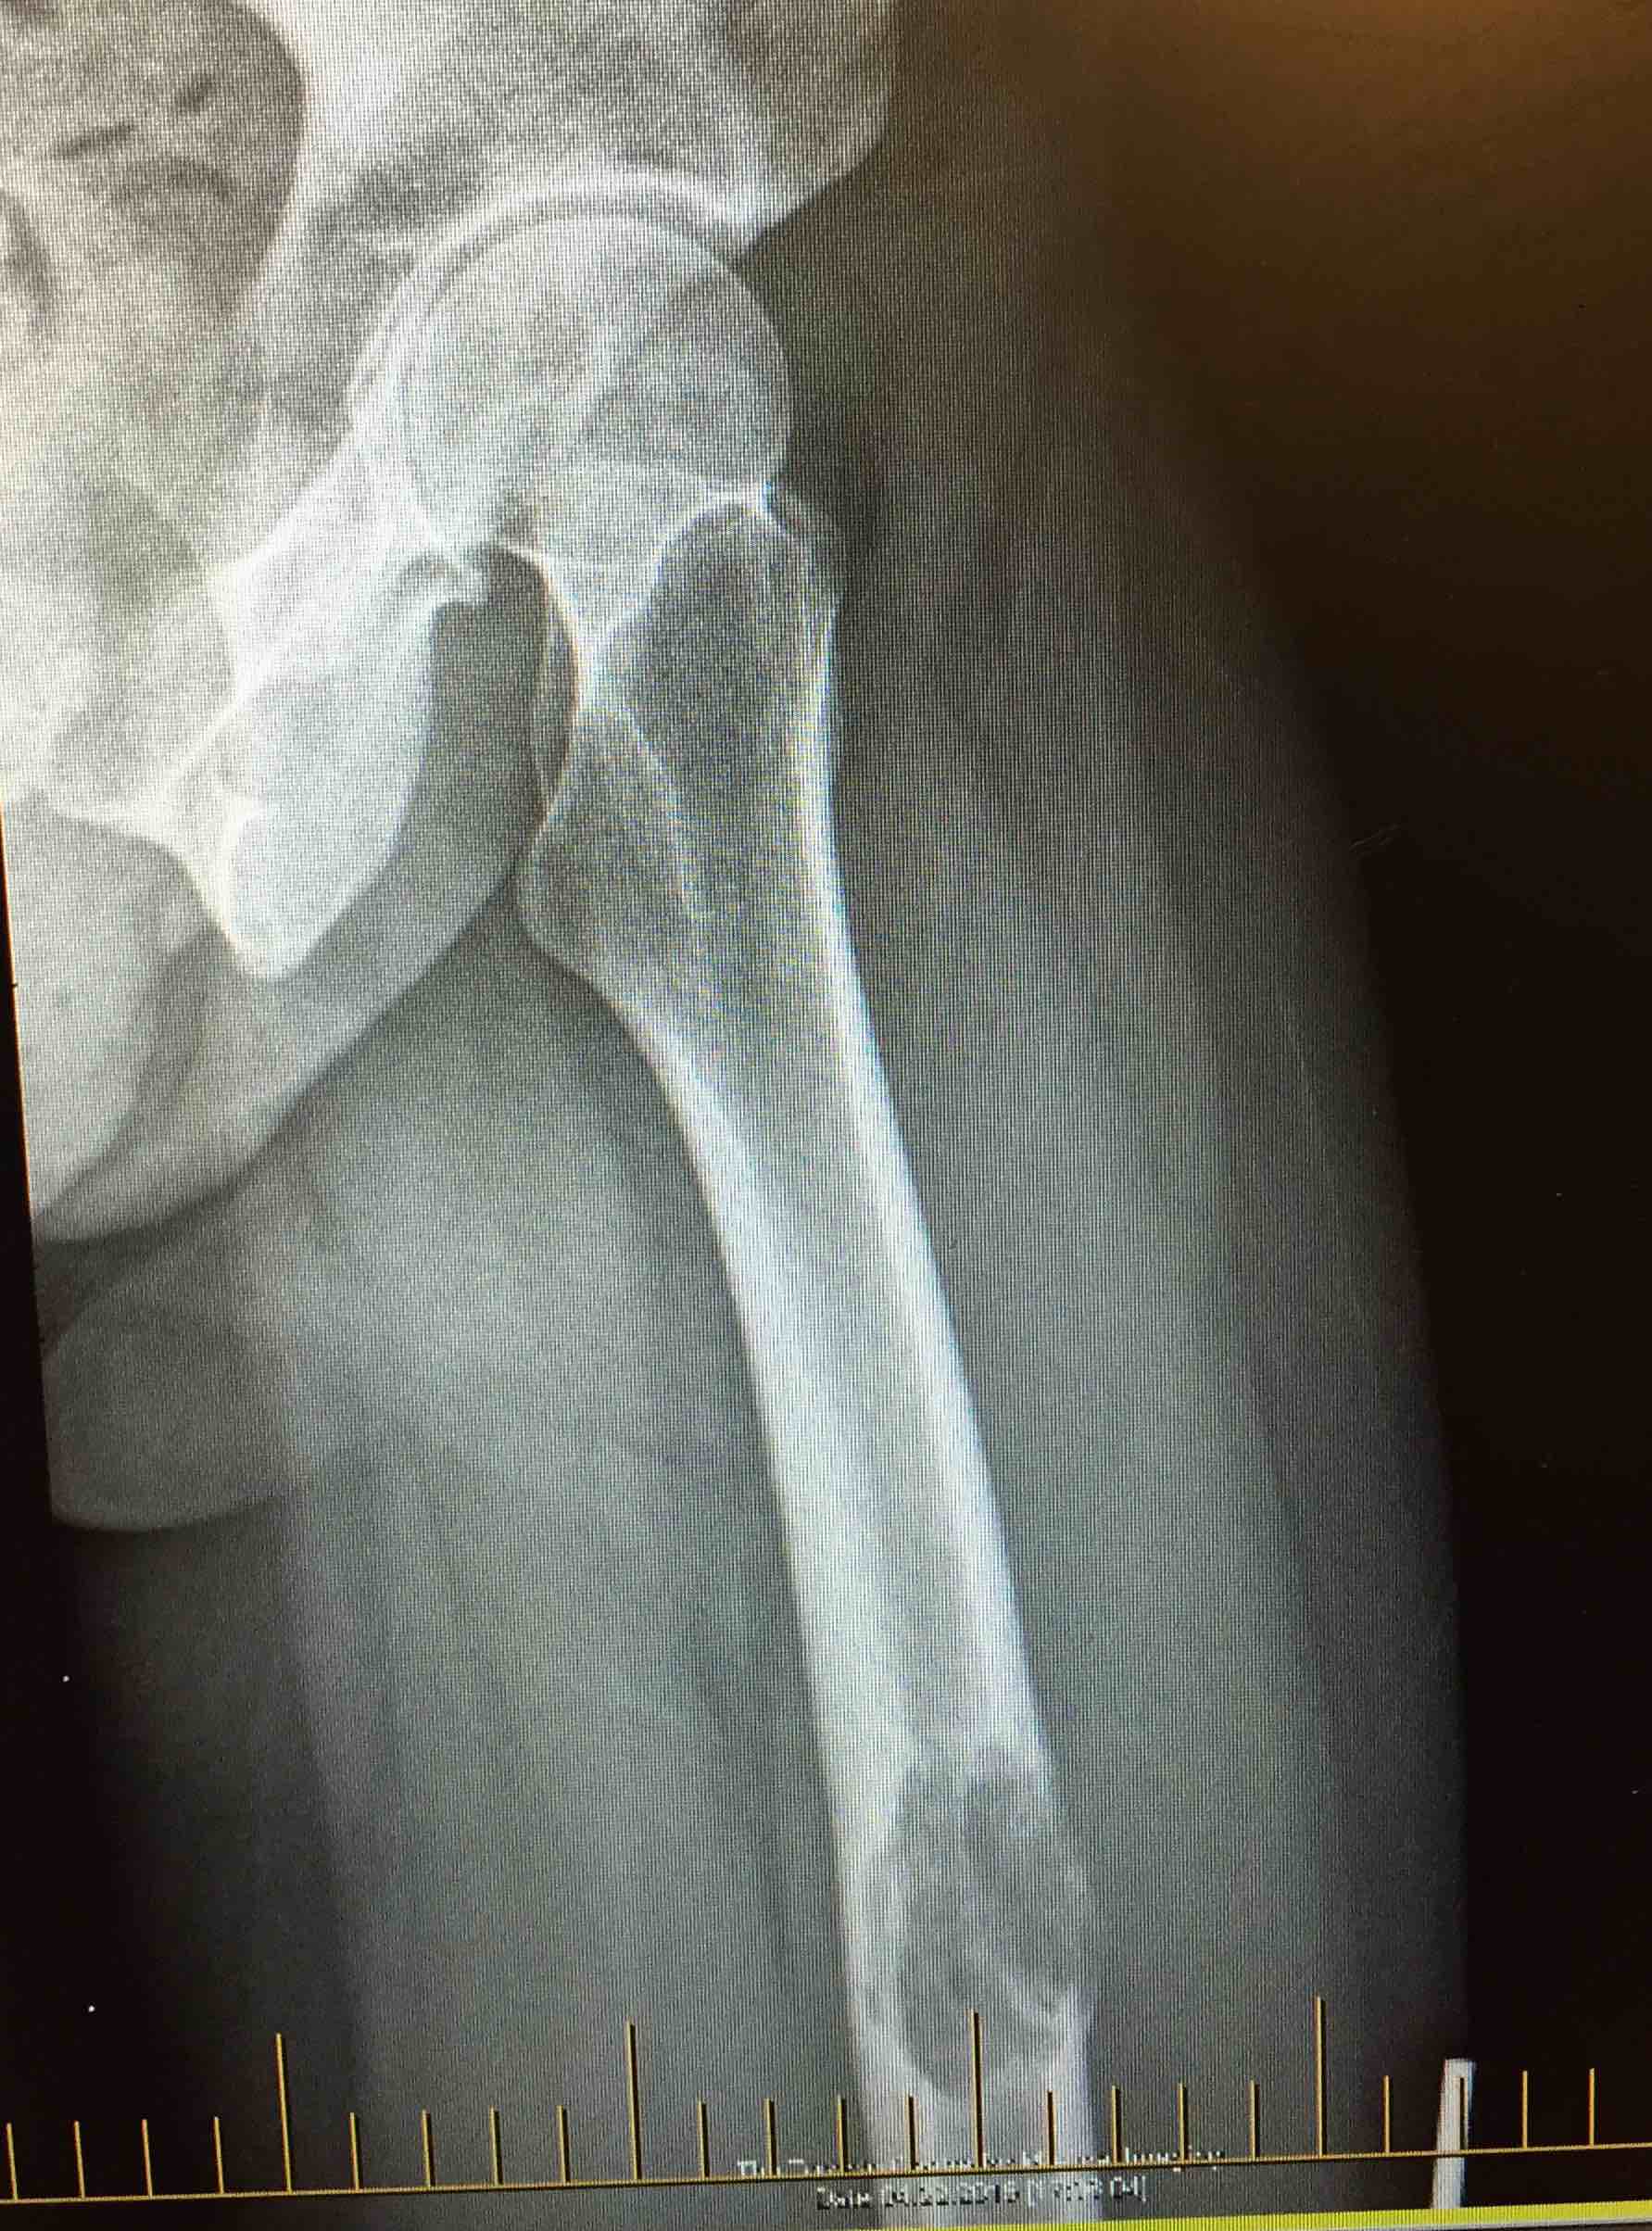

Background

Aim

The identification of skeletal metastasis & fixation prior to fracture

Incidence

50% of new cancer cases have metastasis

- 1% have pathological fracture

- increasing with more aggressive palliative care